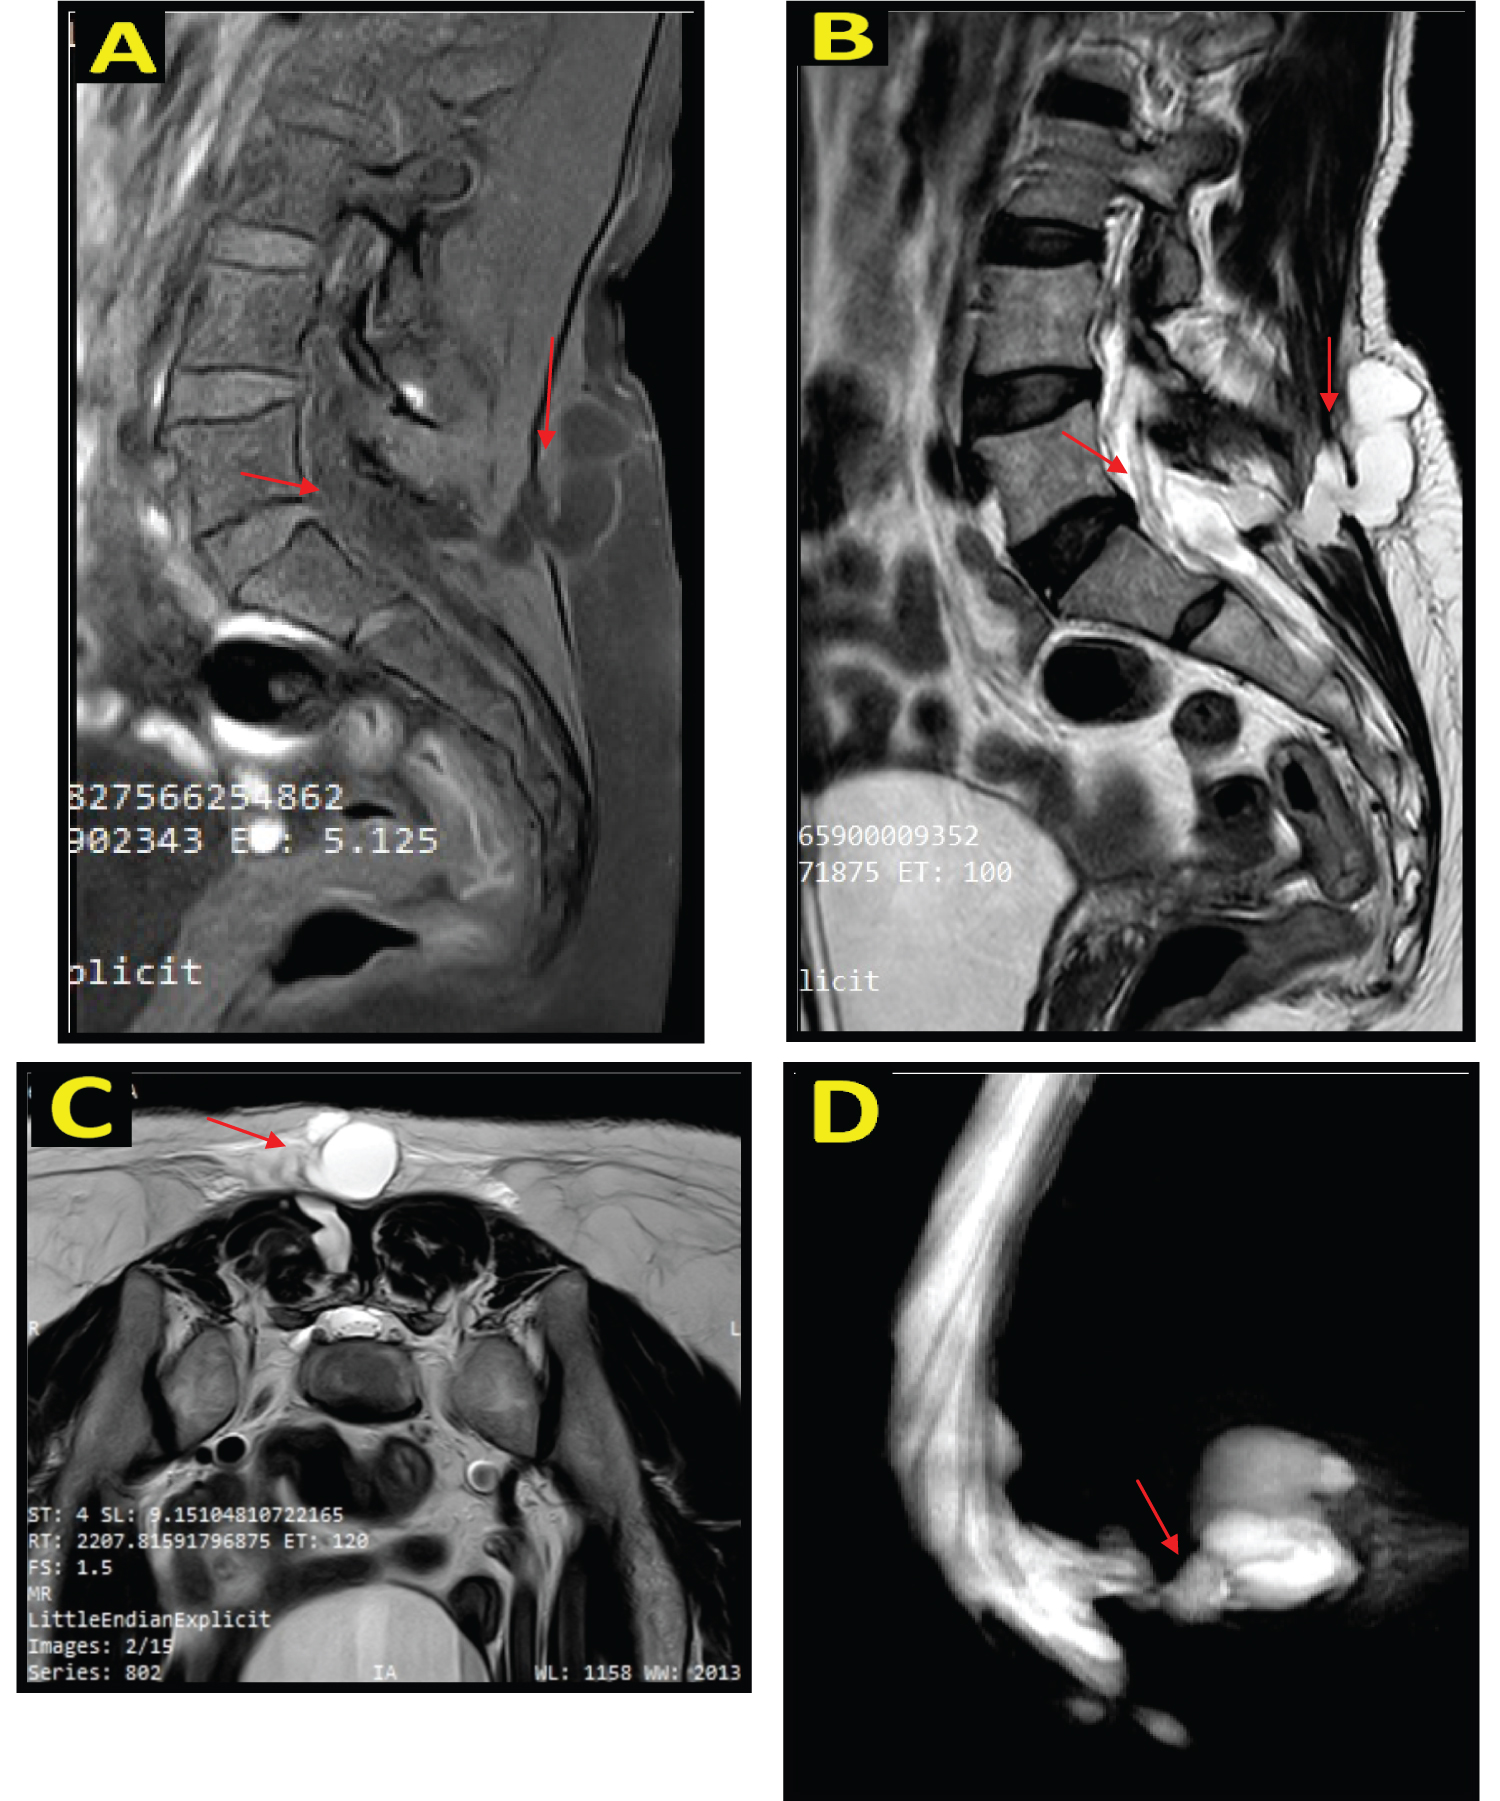

A 48-year-old woman came to the hospital with complaints of lower back pain since 2 months ago. The pain was felt radiates to the lower limbs accompanied by a stabbing feeling, the pain was felt intermittently, the pain worsens at night especially when sitting and sleeping in a soft place, and the pain was reduced when the patient stands up. The patient had a previous history of PSLD surgery at another hospital 3 months ago due to HNP (Figure 1). 6 days after surgery, the patient felt headache, nausea, vomiting, and fainting. Normal bowel and bladder, no history of trauma. On physical examination, there were no lumps in the lumbar spine, motoric and sensory was normal.

Figure 1: A) Sagittal T2 MRI image shows protrusion of the intervertebral disc at L4-L5 and L5-S1 levels; B) Axial T2 MRI image shows protrusion of the intervertebral disc at L5-S1 level towards the posterior central. View Figure 1

The patient underwent a MRI lumbosacral without contrast and a pseudomeningocele appeared in the posterior sacral region. The MR myelography showed no stenosis, and CSF herniation from a defect at the level of CV S1 was seen (Figure 2). The patient then underwent open repair surgery. During the operation, the patient was in a prone position under general anesthesia, a linear incision in the lumbosacral region was made 12 cm long, and a cystic mass appeared in the subcutis area. Then, we freed the cyst wall from the surrounding tissue, cut the cyst wall, and clear CSF fluid came out of the 1 cm defect. The defect was closed by overhecting the dura mater and fascia, then a fibrin glue was applied (Figure 3). Next, the neurosurgeon performed sutures to the muscle, fascia, subcutis, and skin.

Figure 2: Non-contrast lumbosacral MRI image on sagittal section, hypointense lesion on T1WI (A), and hyperintense on T2WI (B). On T2W1 axial view, posterior to CV L5, relatively firm borders, regular margins, with a diameter of +/- 4.4 cm, The impression comes from a defect in the spinal cord at the level of CV S1 (C). On MR Myelography, no stenosis was seen and CSF herniation is seen from a defect at the level of CV S1 (D). View Figure 2